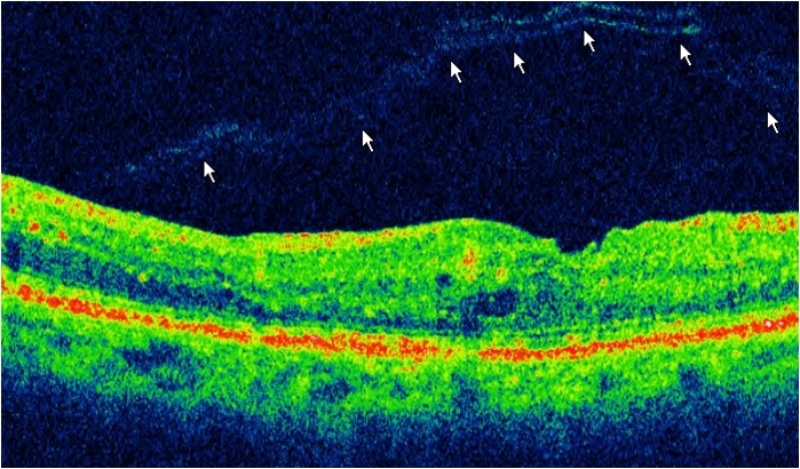

Tras nueva exploración oftalmológica, la paciente refirió un mejor control glicémico por parte de su endocrinólogo así como una sensación subjetiva de mejoría de la visión en su OI sin clínica de metamorfopsia. Presentaba una AV de 0.5 dif en OD y 0.4 en OI con corrección óptica. A nivel funduscópico presentaba un mejor aspecto a nivel del polo posterior en su OI. Tras realizar una nueva OCT macular pudimos observar como se había producido un desprendimiento espontáneo de la hialoides posterior, recuperándose el perfil foveal tomográfico de forma espontánea (

Figura 3). Anulamos la intervención quirúrgica programada y la paciente siguió controles periódicos en consulta externa. A día de hoy continúa con una AV de 0.4 en OI sin metamorfopsia.

Figura 3. OCT macular tras la resolución espontánea del STVM. Se aprecia algún mínimo cambio cistoideo central así como el desprendimiento de la hialoides posterior (delimitado por flechas en la imagen).